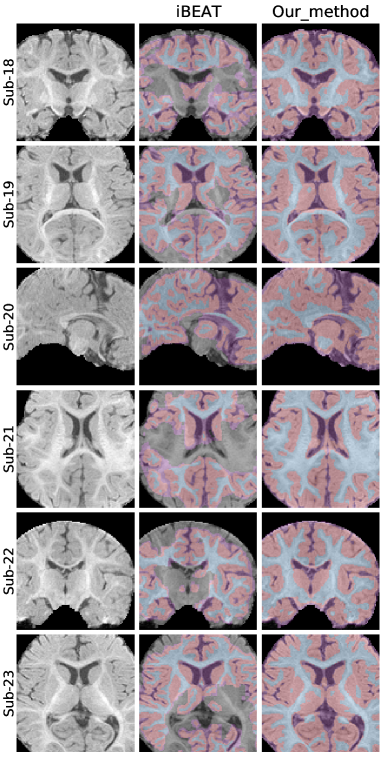

5.2 Qualitative comparisons on raw infant data

To provide a clear visual assessment of segmentation performance, we present a diverse set of qualitative results obtained using different methods. Figs 4 and 5 illustrate a side-by-side comparison between the competing approaches and the silver-standard ground truth generated by Infant FreeSurfer. Specifically, we highlight the 30 most discordant MRI volumes, identified as those exhibiting the highest variance in DICE scores across the evaluated methods when compared to Infant FreeSurfer segmentations. By focusing on these challenging cases, we enhance the visibility of key differences in anatomical structure delineation, allowing for a more insightful comparison of method effectiveness.

This visualization strategy ensures that performance disparities between compared approaches are clearly distinguishable, providing an intuitive and informative perspective on the strengths and limitations of each method, including our proposed solution.